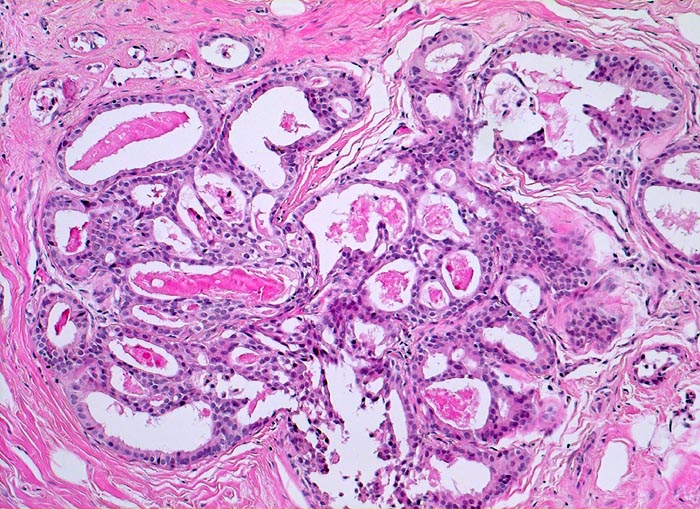

Ausgeprägte Fibrose und zystisch erweiterte Gangstrukturen in organoider Anordnung.

In der Mitte rechts einige Gänge mit gewöhnlicher intraduktaler Epithelhyperplasie ohne Atypie: Polymorphe, sich überlagernde spindelige Zellen. Fliessende Anordnung der Zellen. Schlitzförmige und irregulär geformte Lumina.

Herdförmig apokrine Metaplasie des Drüsenepithels: hochprismatische Zellen mit sehr reichlichem feingranulärem eosinophilem Zytoplasma und runden Kernen.

Im Zentrum des Präparates stark erweiterte Gänge mit intraduktalen peripheren Papillomen.

Alle Drüsen zeigen eine erhaltene äussere abgeflachte Myoepithelschicht mit hellem Zytoplasma.